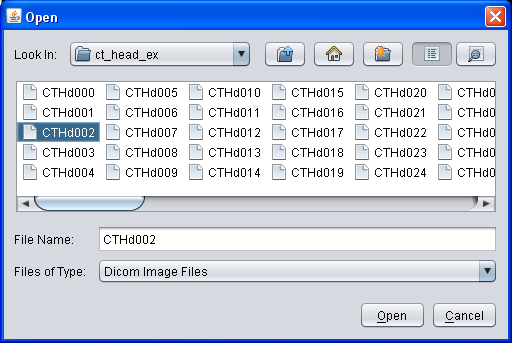

To zoom into a specific region, move your mouse cursor

over the center of your interest and use the mouse wheel to interactively

zoom in and out. Use the right mouse button

to move the magnified region ("panning"). During panning, an overview will

blend in to show your current location in the whole picture. Alternatively

you can enter a specific zoom factor in the element in the "View 2d" title

bar.

Experts Tip: Use the Viewport2d "scaling quality" in the Settings window to enhance zooming quality! This might reduce the rendering speed drastically if the graphic card does not support bilinear/bicubic filtering. |